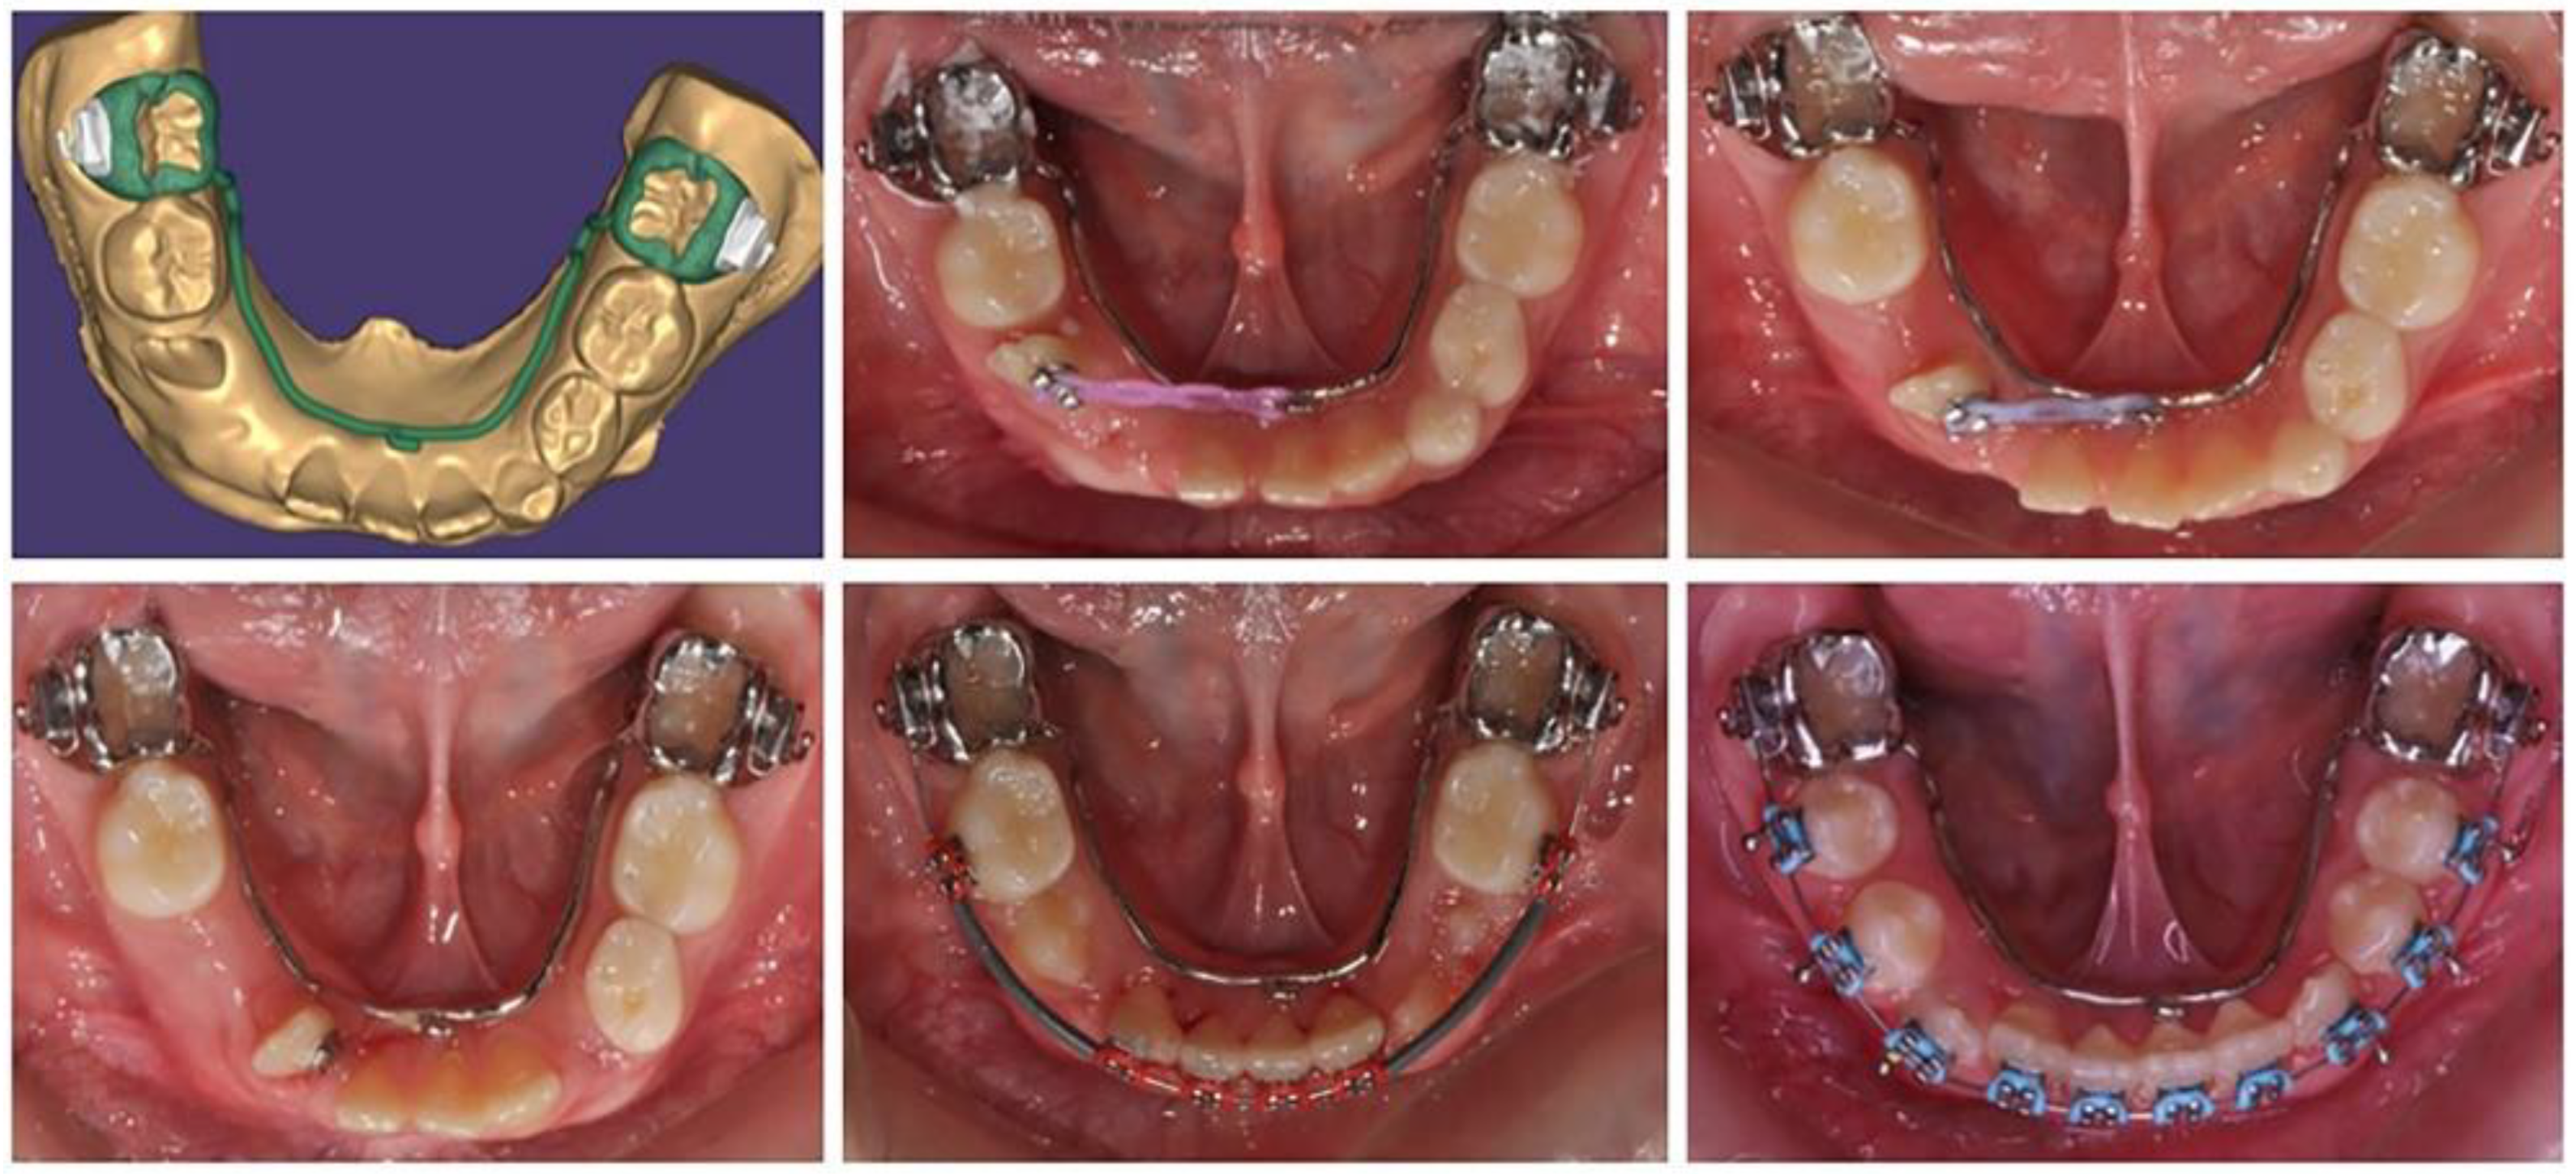

Based on the patient’s digital model, a lingual arch design was made with a hook in suitable location and direction to ensure the desired tooth movement of the lower-right lateral incisor (Figure 2). The body of the PDaA was maximally reduced, but at the same time, it was stable enough to be an anchorage. The patient adapted to it in a short period of time, and the biomechanical system used showed a good result.

Figure 2.

Treatment progress in insertion of a lower-right lateral in the dental arch, using a lingual arch support.

After moving the lateral incisor to its normal location in the lower dental arch, the levelling with the utility arch was able to proceed. This was followed by the eruption of the canine and both premolars. The treatment ended with the complete levelling of the dental arch.